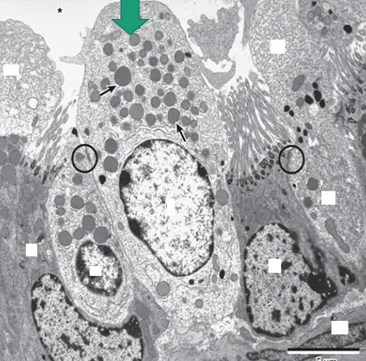

TEM photo of cells lining small bronchiole:

cubical ciliated cells and Clara cell